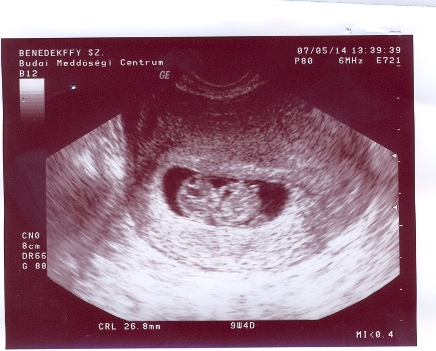

Csajok!

Itt vannak és az enyémek!!!!!!

26,8mm-es az egyik a másik 25,3mm-es.Méhszáj zárt,koruknak megfelelőek és már most hyperaktívak voltak,annyit mozogtak!